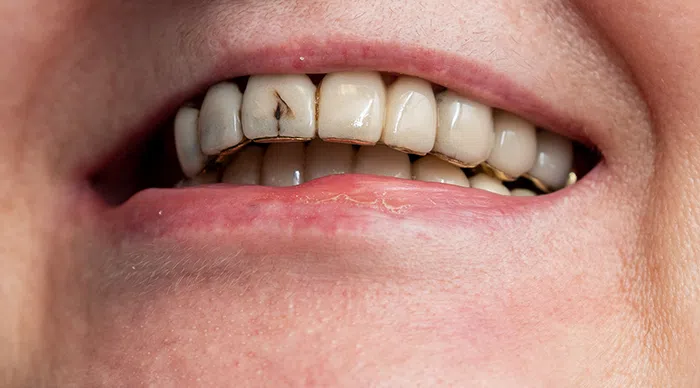

Caz estetica dentară – Coroane de zirconiu și ceramică E-Max

Provocarea acestui caz a fost în corecția asimetriei gingivale, rezolvarea problemelor parodontale datorată lucrărilor vechi metaloceramice, închiderea spațiului dintre incisivii centrali și vindecarea unor chisturi voluminoase la nivel osos în urma unor tratamente de canal incorect făcute.

Pacientul a beneficiat de corecție gingivala cu laser pentru asimetriile gingivale, tratamente endodontice de canal sub microscop, obturațiile vechi (plombe) schimbate cu materiale de compozit cu particule nanoceramice și coroane de zirconiu ceramică, tratarea bolii parodontale prin chiuretaje gingivale cu laser.

Termen de finalizare 2 săptămâni de la amprentarea finală.